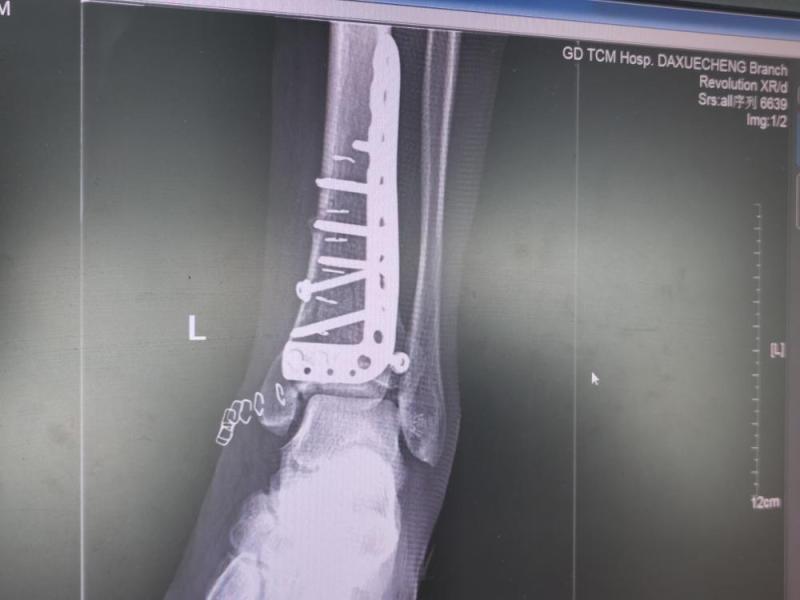

2021-12-5于广州。8月12号回老家搞卫生,竹梯滑倒,腰椎第三节、左脚踝两处粉碎性骨折。17号做腰椎手术;25号做脚手术。mmexport389100b211c86de170312e1ed1e20a2a_1638673815425.jpegmmexport0347dfcbb31fc8eb9e380366fcaec263_1638673765150.jpegIMG_20211125_171501.jpgIMG_20211125_171455.jpgmmexport75d5288bd89d48dc16372b3836ffe6b4_1638673806714.jpegmmexport4c673f93ee4b34f586b44bae5b0370c7_1638673803462.jpegmmexport9a340c98bf210654c6ef7589703ed26f_1638673799559.jpegmmexport0e2d545bf4140643cc9264ec87fbec06_1638673779662.jpegmmexport5e12b0e3a02e0de7e94a47f9e6c1ced5_1638673775301.jpeg